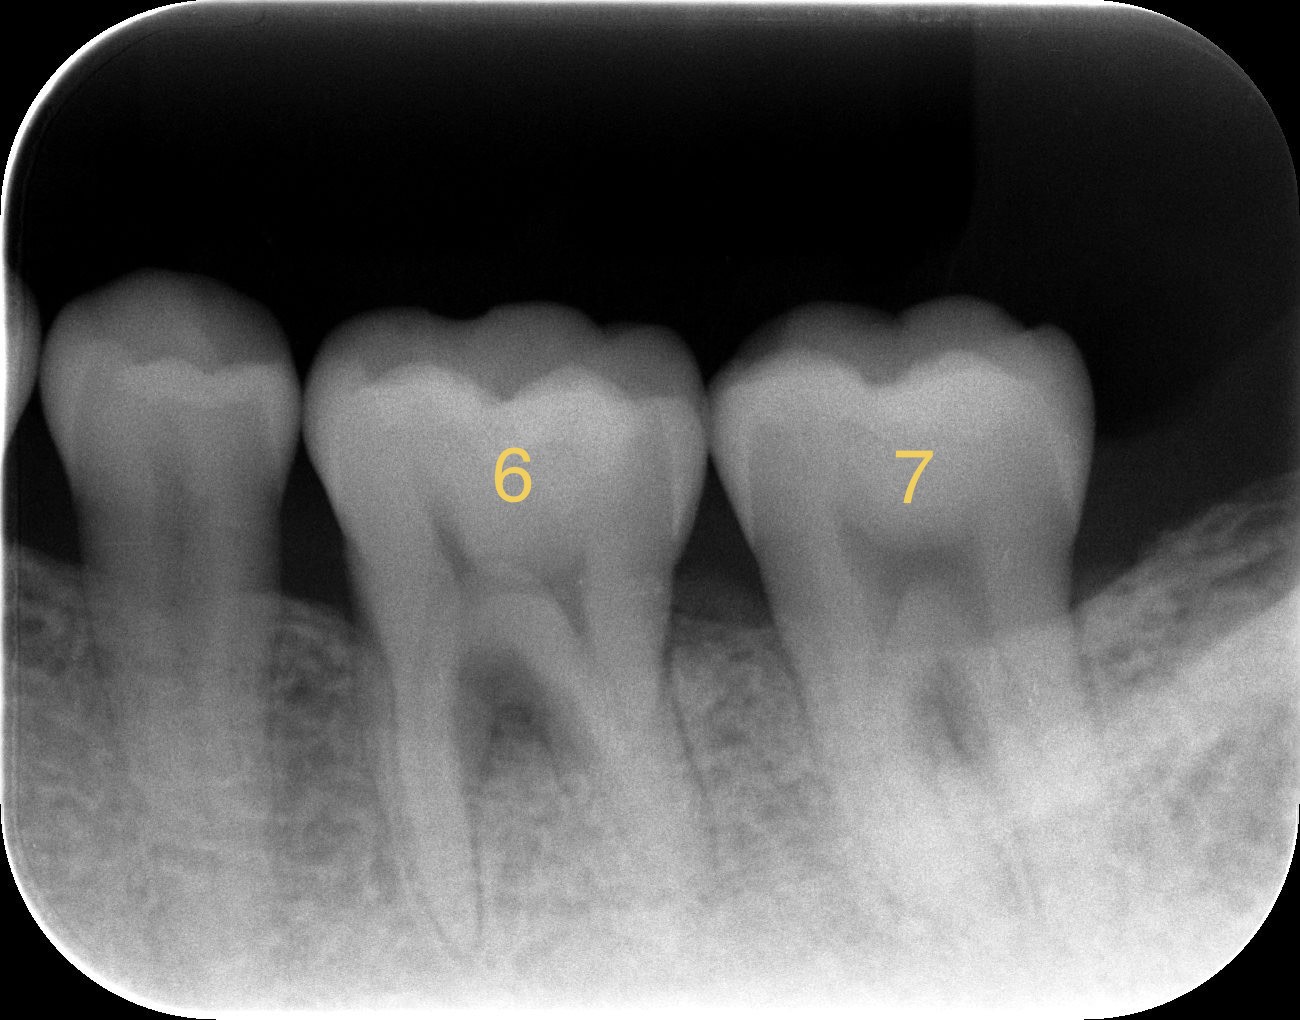

1. 術前の検査(レントゲン)

レントゲン写真を見ると、歯の根の周りの骨がくさび状に黒く影になっているのが分かります。これが骨が溶けているサインです。

レントゲンに写らない理由: レントゲンはカルシウムなどのミネラル成分に反応して白く写ります。この段階では「骨のベースとなる柔らかい組織はできているが、まだカルシウムが十分に沈着していない」ため、レントゲンを透過してしまい、黒く(骨がないように)見えているだけです。

3. レントゲンで確認できるまでの「タイムラグ」

組織再生には明確なタイムラグがあります。

ポケットの改善(軟組織の治癒):術後1〜3ヶ月程度で実感しやすい。

骨のレントゲン上の変化(硬組織の成熟):早くても術後6ヶ月、はっきりと白く確認できるようになるには9ヶ月〜1年以上かかるのが一般的です。